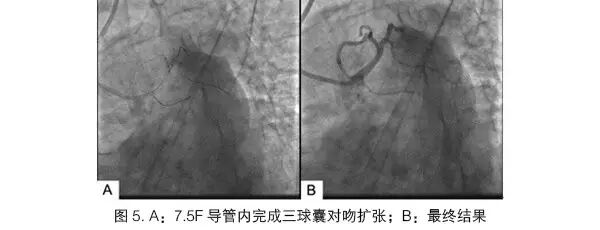

北京友谊医院心血管中心在国内较早使用6.5F和7.5FSheathless Eaucath导引导管,完成的病例多为冠状动脉复杂病变[7],包括CTO、分叉、迂曲钙化病变等,无一例输送失败,也无桡动脉严重并发症出现。而且,我们发现使用4F鞘管完成造影后通常也可以使用7.5F Sheathless Eaucath导引导管。但不建议使用6F鞘管,可能会出现穿刺部位渗血(因为7.5F Sheathless Eaucath导引导管外径小于6F鞘管)。在处理CTO、迂曲钙化等病变时,由于该导管管壁较厚,支撑力很强,在许多病例中,即使使用JL和JR等GC也可获得较强的支撑力,能完成PCI术,更强支撑力的GC有PB、SPB、AL、SC等。7.5F Sheathless Eaucath导引导管的另一优势是在分叉病变的PCI中,等同于普通GC 7F的管腔,而且其内腔非常光滑,输送器械非常方便。7.5F导管能完成大多数的分叉病变技术,例如:直径分别为3.5 mm和3.0 mm的支架可以直接完成经典Crush技术(图4),无需球囊过渡(Step Crush技术);直径4.0 mm的球囊和3.0 mm的支架也可以在腔内完成Reverse Crush技术。部分患者还使用了三个球囊同时对吻扩张(图5)。使用7.5F无鞘导管处理分叉病变,缩短了操作时间,降低了操作难度,也减少了患者的痛苦。